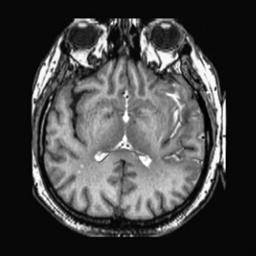

To demonstrate the effectiveness and efficiency of the proposed image fusion method , we conduct a set of comparative experiments on three image datasets. The first is composed by 8 pairs of multi-modal medical images and the second one contains 15 pairs of multi-focus gray or color natural images. These two datasets are often used in many related papers and some examples are shown in Figure 3(a) and Figure 3(b). The third one is a new multi-focus cervical cell image dataset collected by ourselves, which consists of 15 groups of color images and each group contains a series of multi-focus cervix cell images with size of or , etc. Some source examples are shown in Figure 3(c). Our source code implemented in C++ along with the new multi-focus cervical cell image dataset is available online.

We first evaluate the performance of the proposed method under varying total number of octaves and number of layers sampled per octave. The fused images of a pair of multi-modal medical images with different and are shown in Figure 4. In this example, on the one hand, when only 1 or 2 octaves are involved in constructing the DoG pyramid, the fused images fail to keep the integrity information of large size objects (e.g. eyeballs), while by increasing the value of , the integrity information of eyeballs is preserved. On the other hand, although not as significant as the increase of octave numbers , the fused image can contain more details by the increase of layer numbers . The corresponding objective quality metrics are shown in Figure 5. As shown in Figure 5(a), most of the metric values are improved as the number of octaves increases with the fixed layer numbers 3 in the global tendency and each of them tends to be stable when the number of octaves is 5. To get a relatively good quality from Figure 5(b), we can notice that some of the metric values can get a good performance when the number of layers is 3, such as the MI, SSIM, QI and VIF, though there are only a little change of all the metric values by increasing the number of layers with the fixed octave numbers 5. Because it will result in more computation burden with the increase of the value and , and for different kinds of source images, there are different performance with the diverse parameter settings. To get a trade-off between them in our experiments, we set for the multi-modal dataset, for the natural datasets and for the multi-focus cell dataset, respectively.

Figure 6 shows the fused images obtained by different methods with the multi-modal source images shown in Figure 3(a). As shown in these figures, the proposed method can produce images which preserve the complementary information of different source images well. Moreover, due to the scale-invariant structure saliency selection, our method can keep the integrity information of large size objects and the visual details simultaneously. Although the fused image generated by other methods can also capture the details to some extent, all of them fail to keep the integrity information of large size objects such as the eyeballs. Furthermore, from Figure 6(k)-6(t), the DTCWT, GFF, IM and NSCT methods may decrease the brightness and contrast while the proposed method can preserve these features and details without producing visible artifacts and brightness distortions.